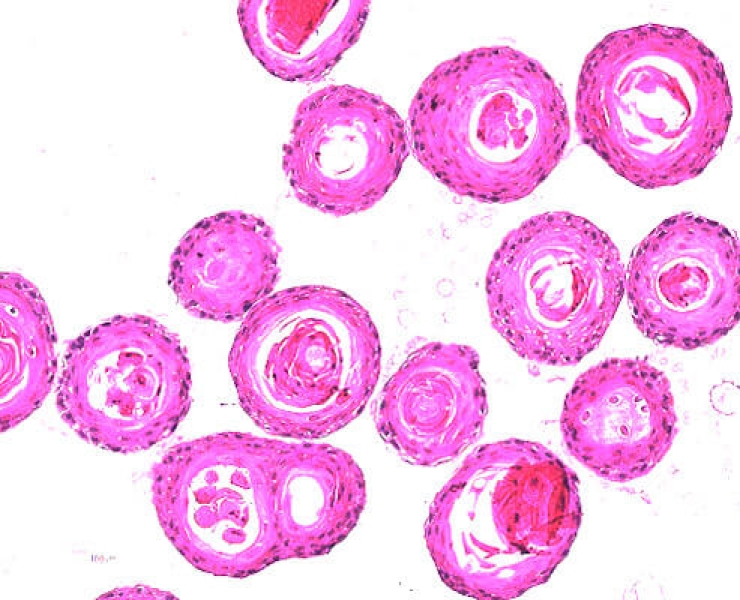

• Link to /sites/default/files/styles/slider_desktop/public/images/slide/he-staining-organoid-mouse.jpg?itok=FQrpS4No

HE staining of organoid from mouse esophagus squamous carcinoma